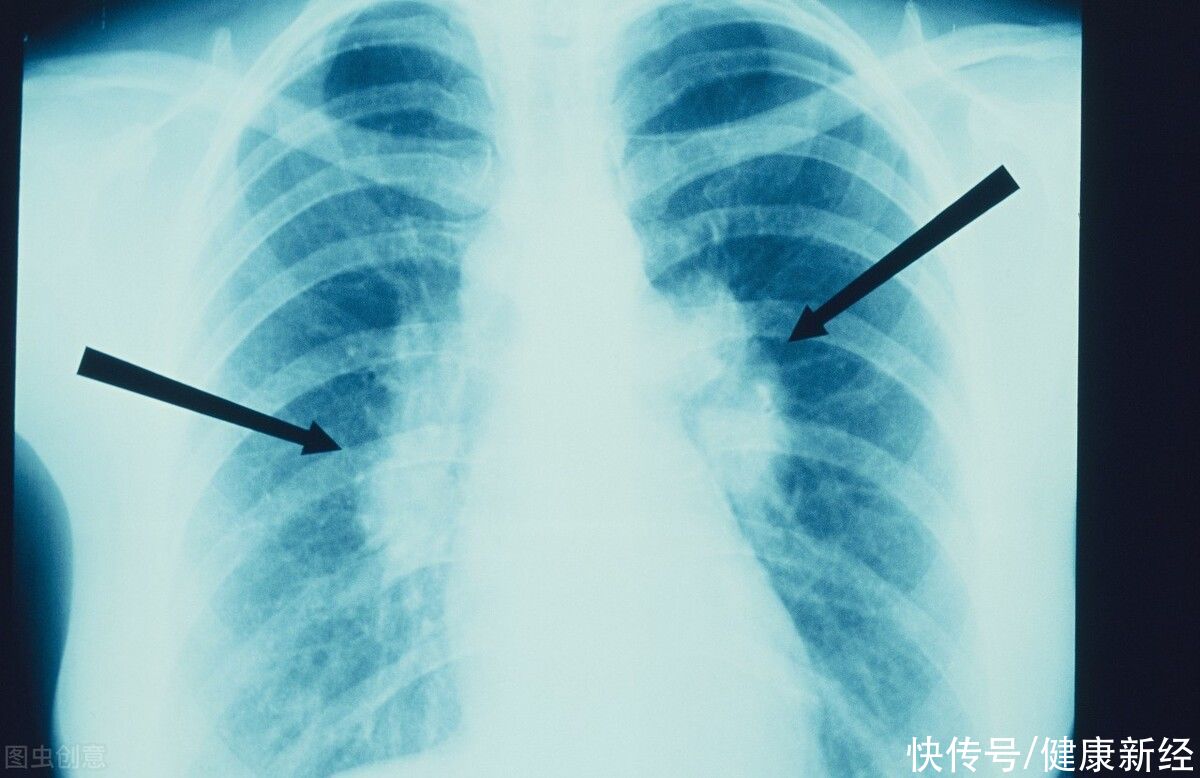

肺结节,可能会导致哪些肺病的发生呢?1. 肺部感染,炎症性假肿瘤。虽然这是一种假肿瘤,但别掉以轻心。主要是慢性炎症引起的。白色的是肺部的细菌或病毒感染。生长一般缓慢,长期难以改变,发病年龄一般不大。

3. 肺癌,结节边缘毛呈滑裂小叶状,密度不均,在短时间内迅速生长,有明显的体征及症状。也可结肠癌及颅内肿瘤肺转移。